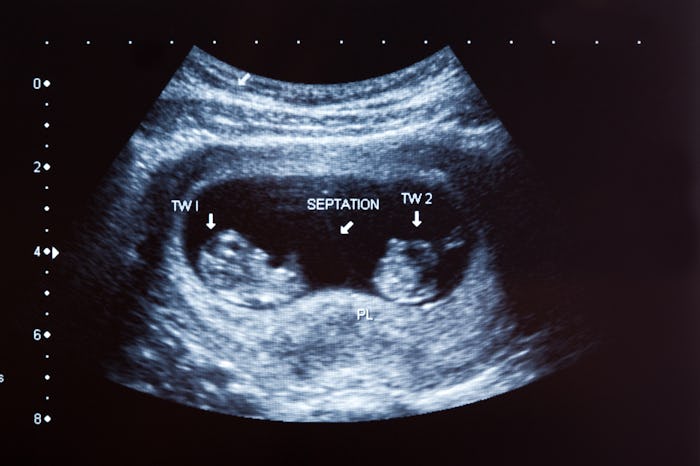

For vaginal delivery of both infants, the twins decide birth order by their placement in the uterus. Once the babies are large enough to stay in one position in the womb, the twin lowest in the uterus is known as Baby A and the one furthest from there is Baby B, according to the Stanford Medicine News Center. In the majority of vaginal births, Baby A is born first. But occasionally the twins switch positions at the last minute, and Baby B emerges first, as further noted by the Stanford Medicine News Center. Still, the birth order is relatively straightforward.